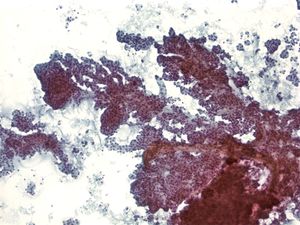

Benign Pancreas – PPANC4-04 Key Cytological Features of benign acinar cells:

- Cohesive, grape-like aggregates singly and attached to fibrovascular stroma

- Scattered stripped naked nuclei

- Basally located round nucleus

- Finely granular chromatin

- Small nucleolus; larger in reactive acinar cells

- Abundant granular cytoplasm

- Indistinct cell borders in clusters